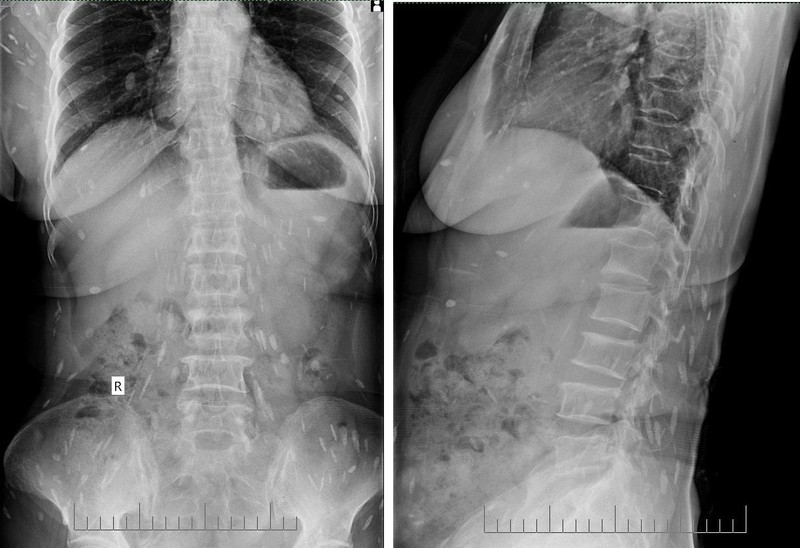

Hình ảnh chụp tim phổi thẳng cho thấy rất nhiều con sán lá gan (màu trắng) ký sinh trong nhiều cơ quan của người phụ nữ. Ảnh: BVCC